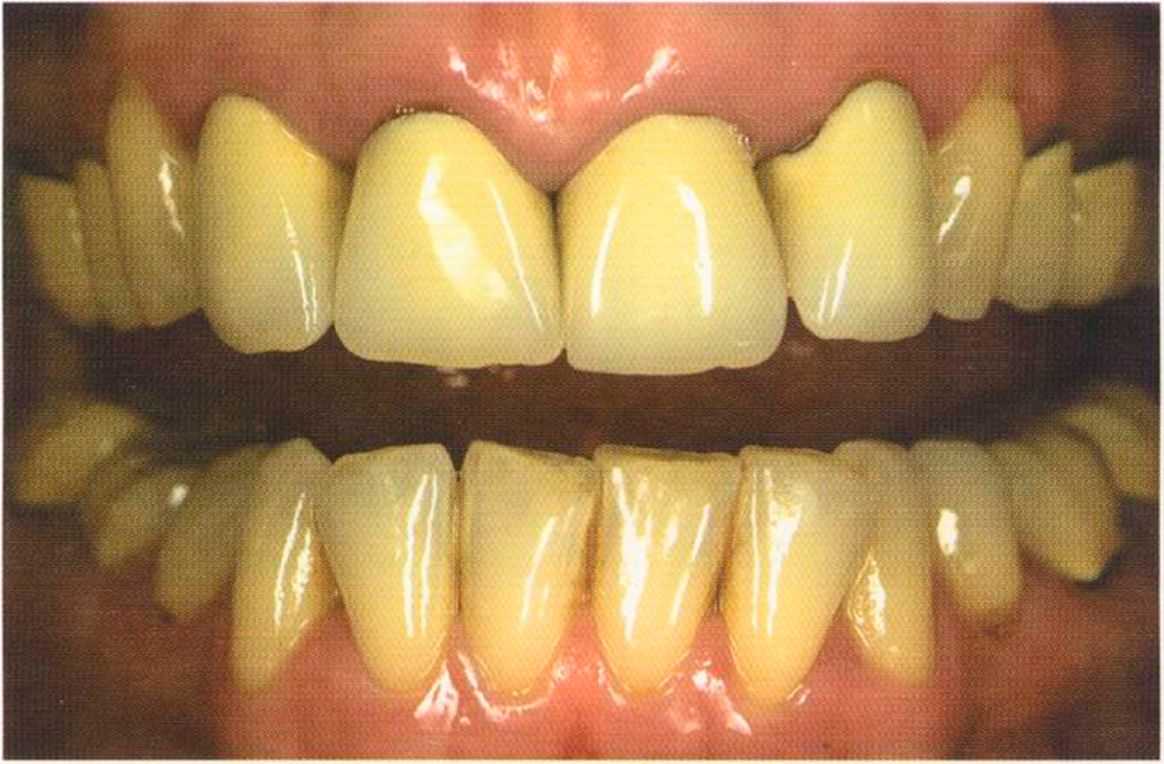

Эта женщина пришла в клинику доктора Лангханке с металлокерамической реставрацией.

Ей не нравились типичные в таких случаях темные края коронок и опаковость керамики.

Коронки выполнялись в моей лаборатории вместе с пациентом. Мы работали долгих четыре часа, чтобы всем понравился результат. Обратите внимание на отражение света по краевым валикам. Мезиальные валики коронки 12 зуба гармонично переходят в дистальные валики 42 зуба. В идеальном варианте «отражающиеся валики» должны проходить по прямой линии. Это привило для всех мезиальных и дистальных валиков фронтальной группы зубов. Оно имеет очень важное значение и влияет на результат нашей работы.

Эти валики проходят перемещаясь, однако по одной линии. Примером здесь являются мезиальные поверхности на коронке 11 и на 31.